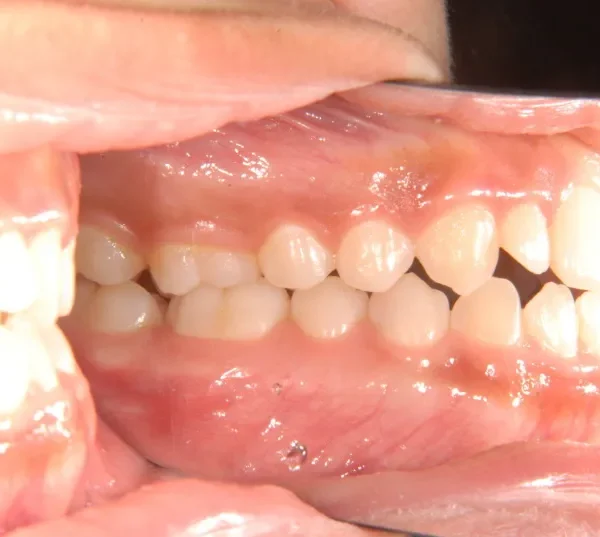

開咬・舌癖・18歳女性

初診時年齢 高校生 (女性) 主訴 開咬 舌癖

状態 前歯で噛めない(開咬/オープンバイト)